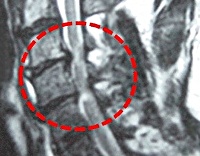

Золотым стандартом в диагностике компрессионной миелопатии является выполнение КТ и МРТ позвоночника. На снимках можно отчетливо увидеть не только причины, приведшие к сдавлению, но и состояние тканей мозга.